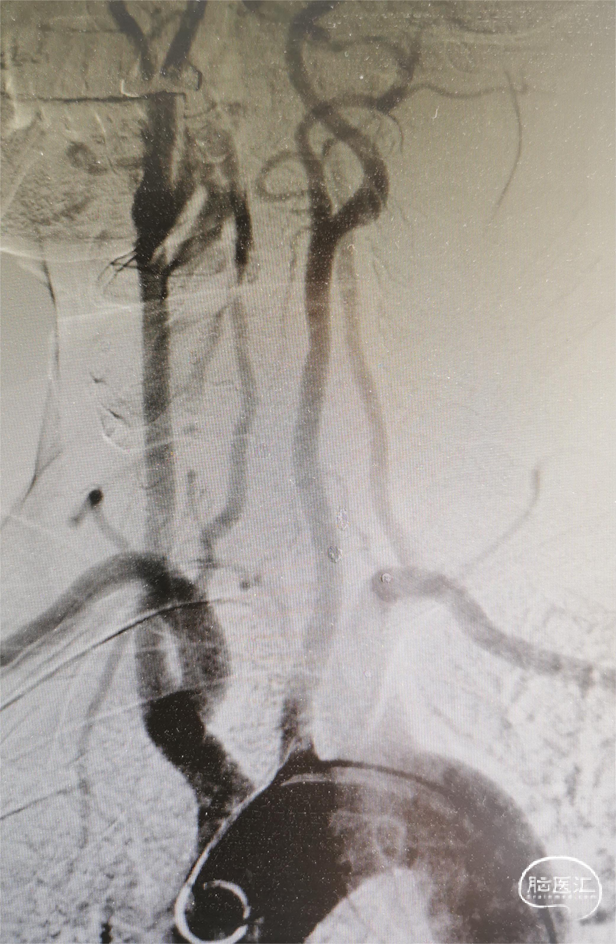

2023.10.19 DSA

患者仰卧位,经右侧股动脉穿刺置5F鞘,分别以5F猪尾造影管置主动脉弓,4F单弯导管置双侧颈动脉、双侧锁骨下动脉造影。

→主动脉弓造影:Ⅱ型弓,单弯导管分别至头臂干、右颈总动脉、右锁骨下动脉,未见明显狭窄;左颈总动脉、左侧锁骨下动脉,未见明显狭窄。

→RMCA供血区显影延迟,供血显著减少。

→右侧大脑中动脉MI远端及M2上干血栓,血流缓慢。

→合并颈动脉蹼。

→左侧颈总动脉发出左侧颈内动脉及左侧颈外动脉,分叉处光滑,未见狭窄,左侧颈内动脉发出左侧大脑前动脉以及左侧大脑中动脉,无明显狭窄,血管走行正常,前交通动脉开发,使右侧大脑前动脉显影。

右侧颈总动脉发出右侧颈内动脉及右侧颈外动脉,右侧颈内动脉C1段、起始部侧壁可见短小薄膜样突出,颈动脉窦血流紊乱,远端血流可,大脑中动脉、大脑前动脉显影可,走形正常,未见狭窄及扩张。